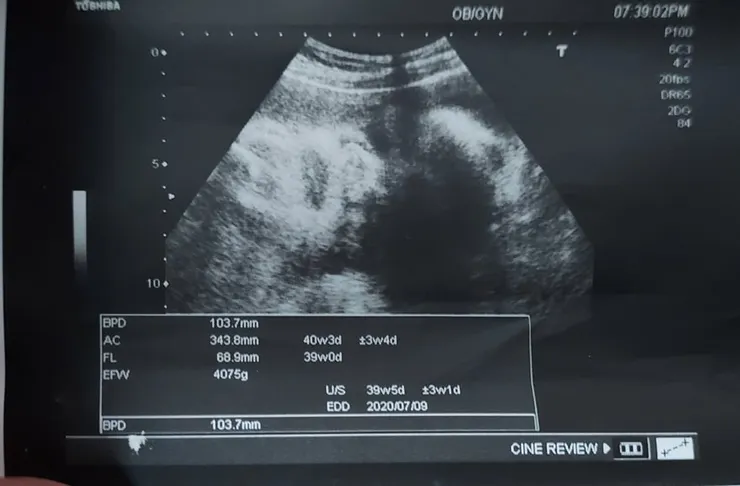

2020.7.01(三)AM8:30 (7.739W--4075G)

天啊,已經七月了欸,我還一直感覺是六月 我的280天APP已經到個位數了,超級感謝大家對我的關心,昨天晚上還有天使和我分享,有關超音波小孩太大的問題 結果剖腹出來也沒真的破四千,似乎多一點繼續抗戰的動力了, 不然昨天聽完醫生的檢查,差點要放棄了,想說算了,隨便吃好了,反正這麼大 都生不出來了,雖然我的醫生一直鼓勵我可以自然試試看,很溫柔的說對媽媽沒有風險,假設第二產程真的不順利,馬上剖腹都可以,而且他說我算高應該有機會可以嘗試, 只是我超級怕來個全餐,他說通常出不出的來他也不會勉強,看當下就會知道有沒有卡住,到時候他會評估真的覺得不行,我們就開刀,我們大家一起看下去,看看這趟信德之路怎麼發展, 我真的是小信德的人,但是我常常練習我的信德,天主請幫助我

今天去產檢醫生說因為寶寶頭大,算起來比較重,目前已經突破4000,但是如果我165好像勉強可以試試看,真的到時候開指生不出來,就只能剖腹,所以我決定現在來吃個麻辣泡麵,明天再來個麻辣鍋,網路上說吃麻辣的很容易促進收縮喔,還有冰棒,希望本週可以出生,但是本週才38,上次醫生說39機率大,喔天啊,再擺下去不就五仟了。

還好網路上有這些介紹 一知半解滿恐怖的,週二去做兩周一次的產檢,兩周前還是2411,本周34周來到3091,一般網路上看到都是2500左右,醫生說頭怎麼大這快 已經9.5CM 大了六周,六周都可以生的頭了 太可怕,有點緊張是不是甚麼大頭症,還是唐氏症,因為想說反正有沒有唐寶寶都要生 就沒羊膜穿刺了,但是聽到結果還是挺可怕了,不過淡定的醫生說再觀察看看 也許之後就不會在大了,也說我比較高有可能生大隻一點的,但還是有點小擔心,不過網路上看到一些孕媽咪,好像也有說超音波也有不準的 心情有被安慰到了,有的是被告知寶寶過大 但是生出來其實還好,不然就是看起來正常 但是生出來過大。

另外和大家分享一下今天產檢終於沒有這麼嚇人了,上次34週說寶寶3091克 頭95.5頭大了四週,因為32-34多了六百克,嚇死我了,30-32很努力吃燕麥才多了300克 後來放鬆一點吃了冰淇淋,布丁 豆花 但是真的都也只吃一點 還是多了600太恐怖,所以34-36週這兩星期我也很努力吃燕麥,今天的數字是 3297克 頭圍 95.9 天阿太幸運了,雖然之前大家都安慰我會有誤差 但是還是會緊張,我也努力相信有誤差 讓自己平安,雖然目前數字自己覺得可以接受 但是表示接下來還是要努力祈禱和克制 進行燕麥人生 超級超級感謝天主,也請大家繼續為我的順產祈禱 因為我真的覺得我是史上最怕痛的女孩。